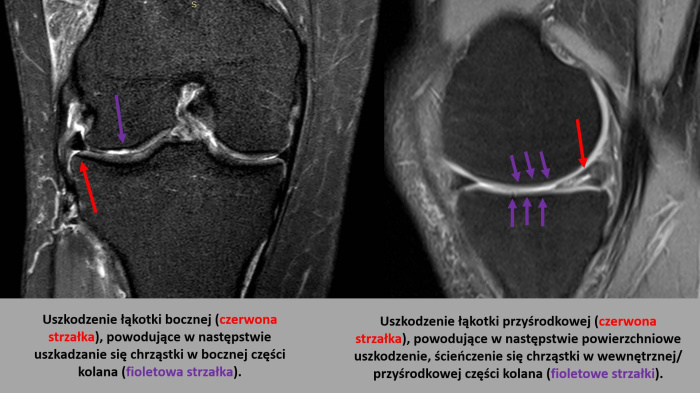

Uszkodzenia łąkotek - dlaczego warto je naprawiać?

Łąkotki to ciche bohaterki naszych kolan. Dowiedz się, dlaczego ich uszkodzenie może prowadzić do poważnych konsekwencji i kiedy konieczna jest naprawa chirurgiczna.